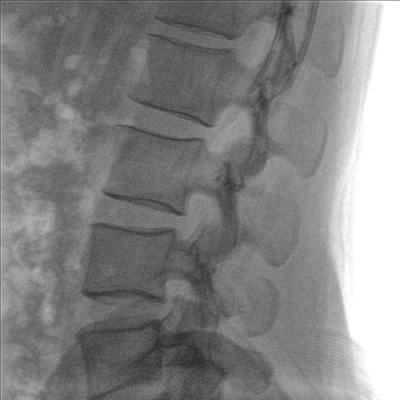

Clinical picture

臨床圖片